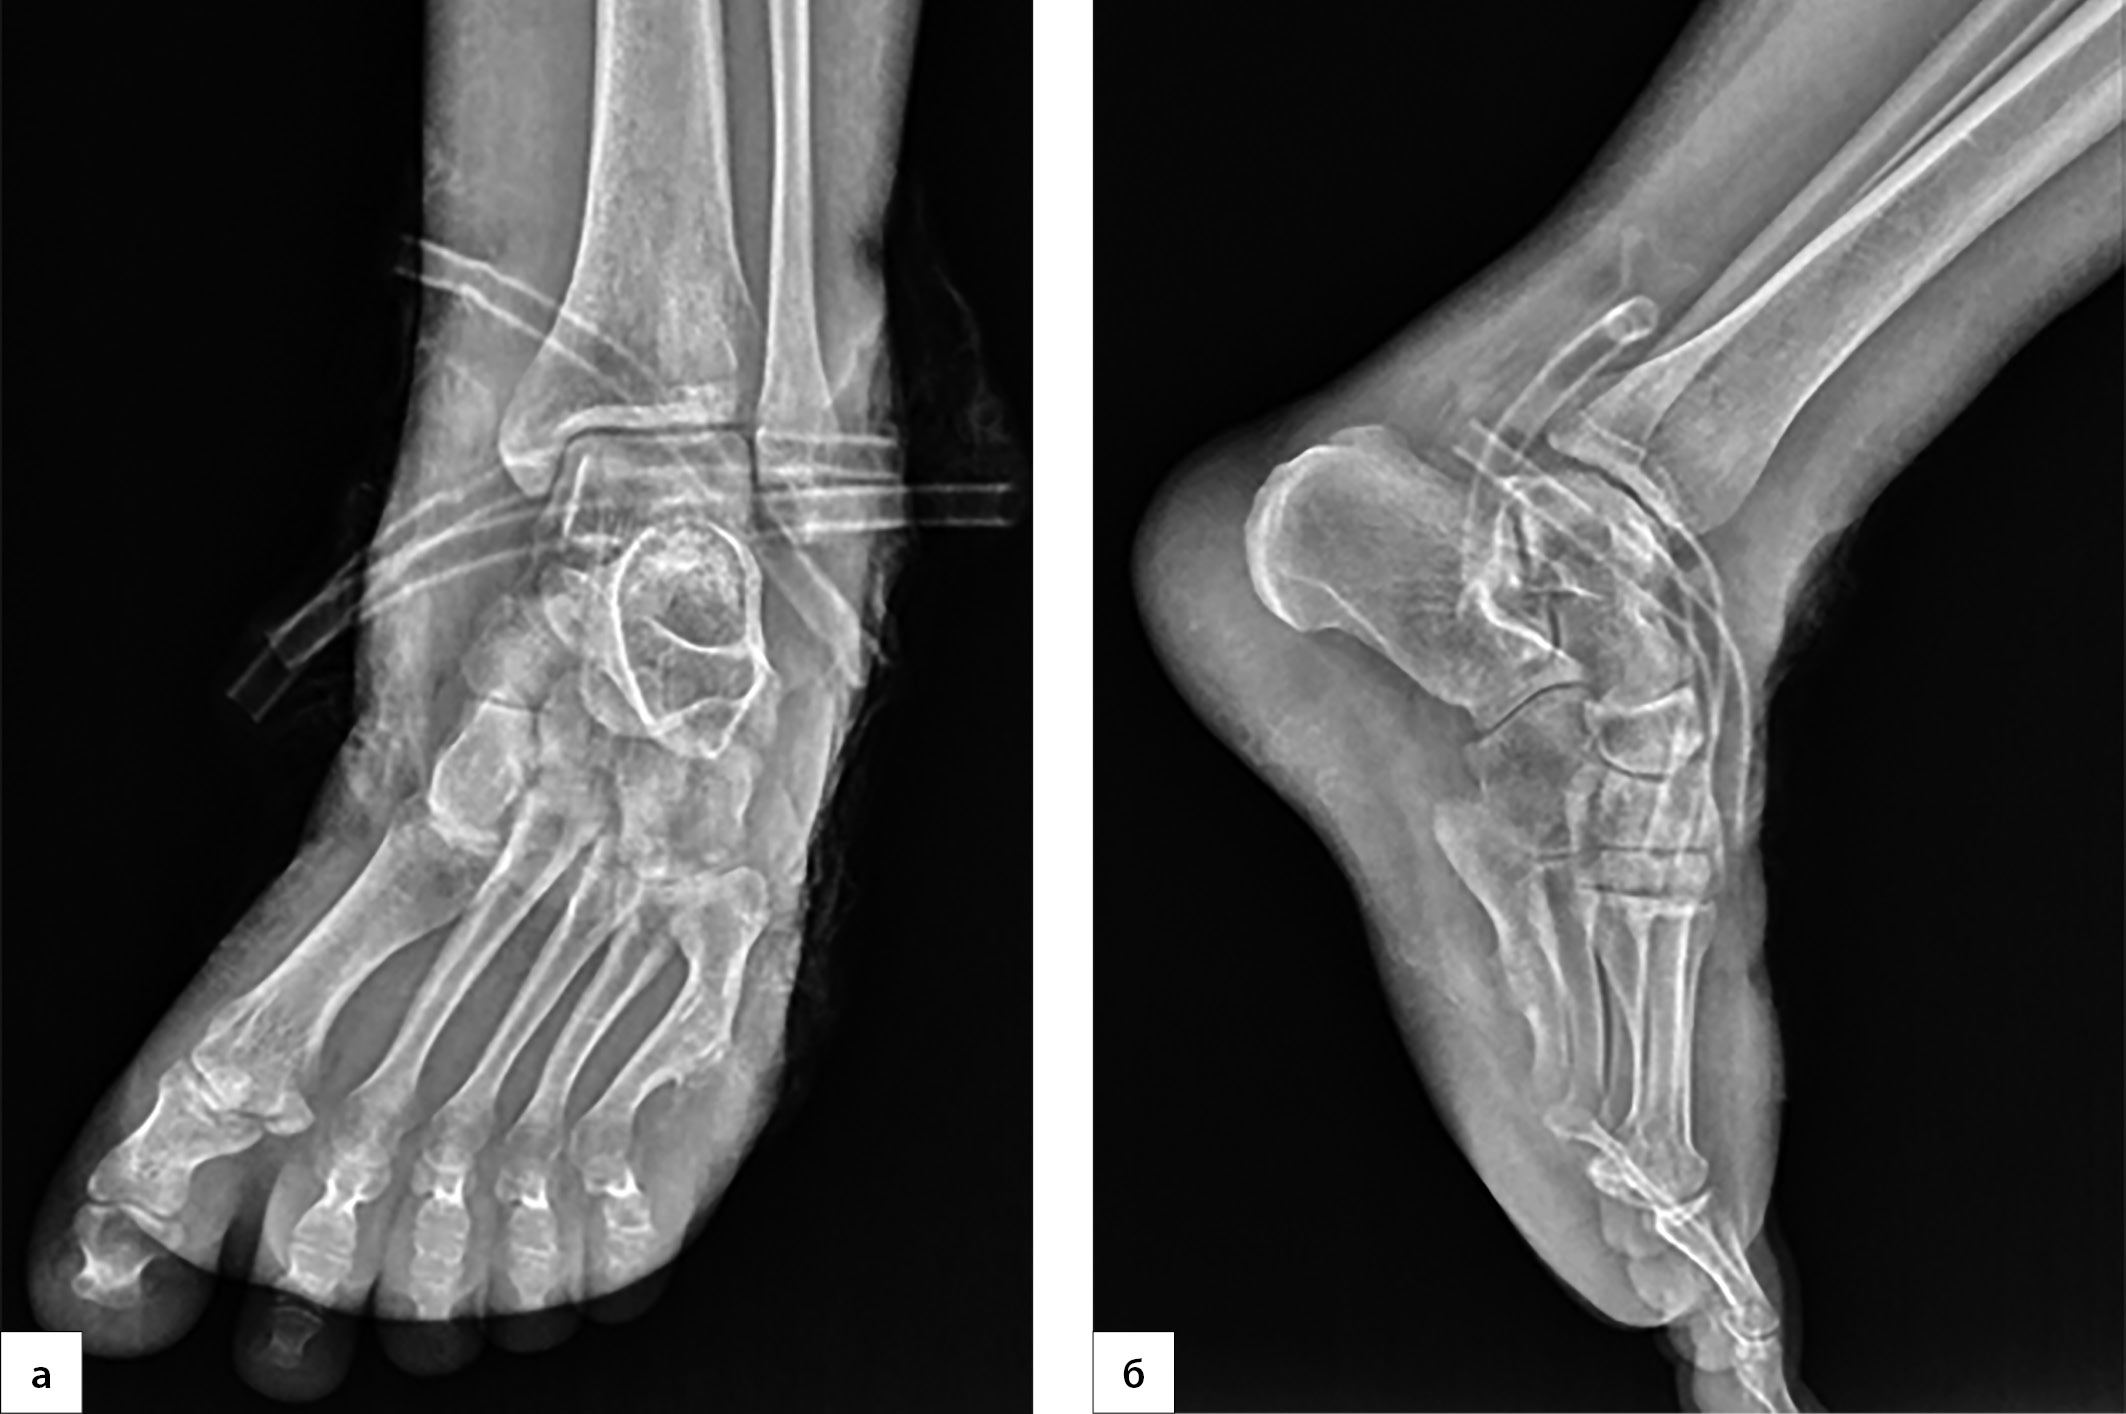

5. Рисунок 5. Рентгенография левого голеностопного сустава и стопы на 20-й день госпитализации. (а) — прямая проекция; (б) — боковая проекция | |